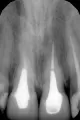

Вы чувствуете дискомфорт в верхнем 6-ом зубе, так как в нем есть воспалительный процесс. По данному рентгеновскому снимку (хронический апикальный периодонтит). Зуб следует перелечить. Проконсультируйтесь очно со стоматологом-терапевтом.

Около месяца назад появился дискомфорт в области зуба со штифтом. Что можно сказать по снимку?

• Два зуба следует перелечить. В одном канал запломбирован не до верхушки корня, что приведет к развитию воспаления в области апикального отверстия. В другом зубе между пломбой канала и штифтом имеется затемнение, возможно штифт разгерметизирован частично.